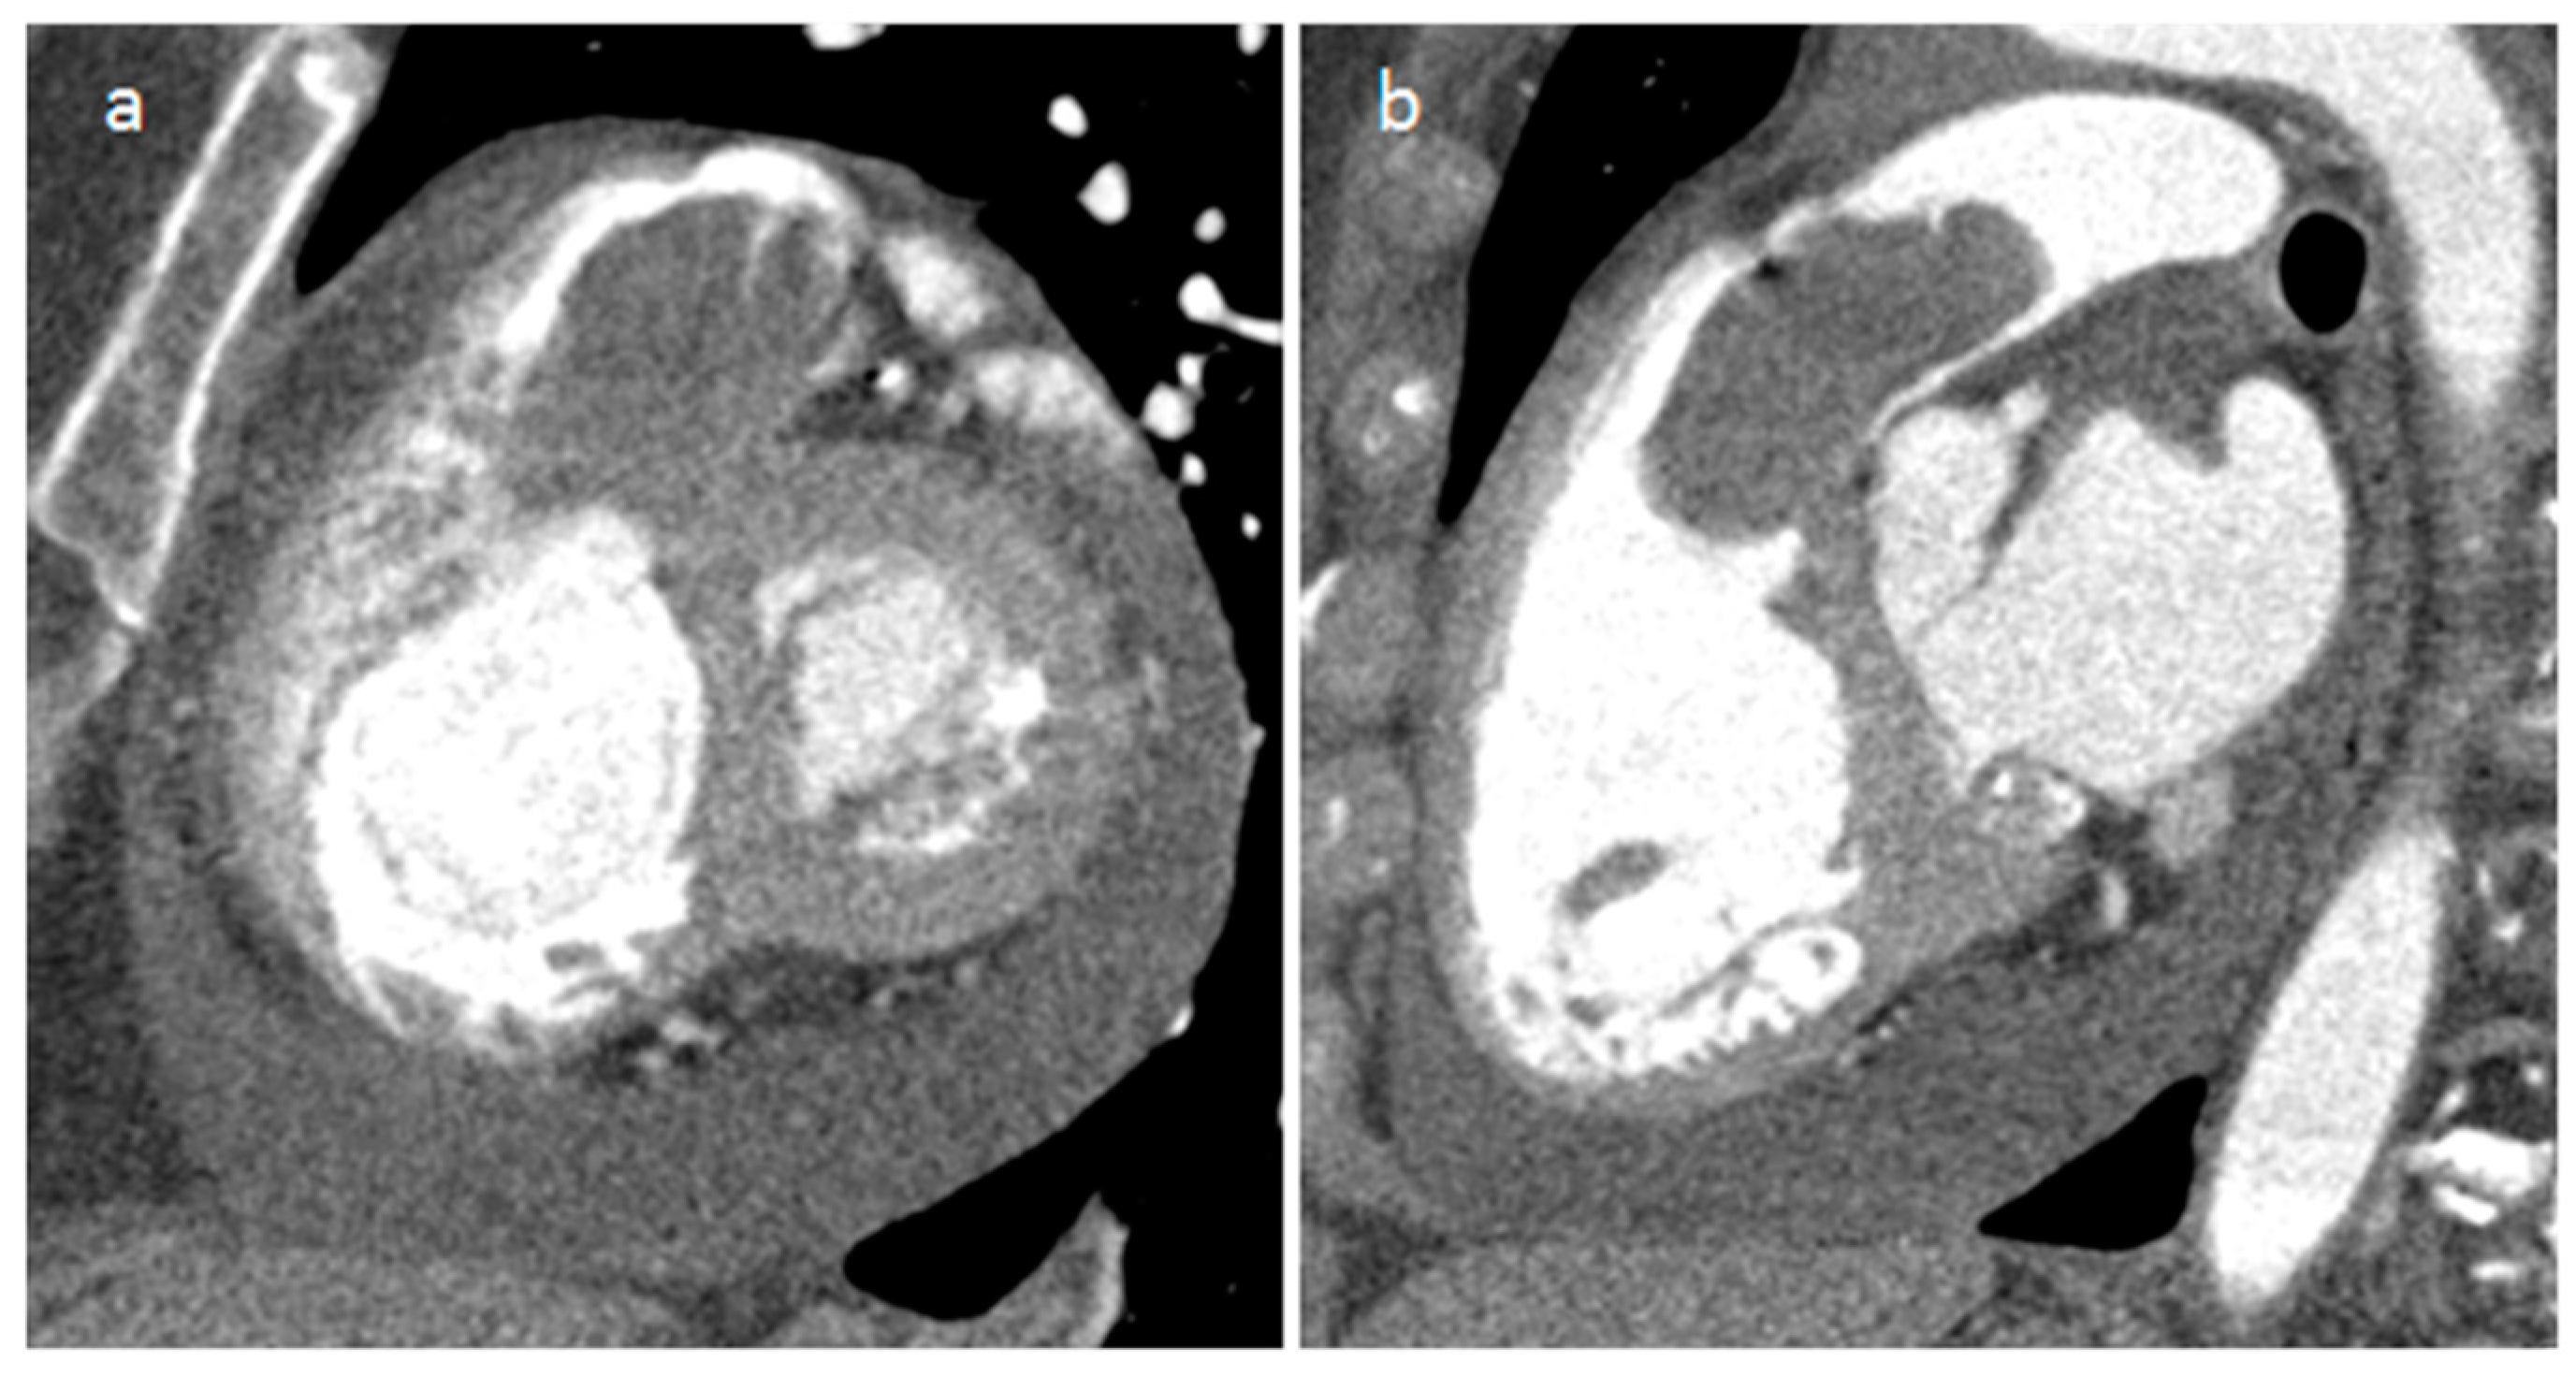

3.3. Mitral Annular Calcification and Its Caseous Degeneration

| Mitral annular calcification | Old patients | annular fibrous ring of the mitral valve | Asymptomatic | Calcifications, mitral valve | Hyperechoic | Calcific mass | Hypo T1w, hypo T2w, peripheral rim enhancement |

| Caseous degeneration of mitral annular calcification | Old patients | annular fibrous ring of the left atrio-ventricular valve | Asymptomatic | Calcifications, mitral valve | hyperechoic | Calcifications within and around the mass | Mildly hyper T1w, mildly hyper T2w, peripheral rim enhancement sometimes with central enhancement |